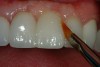

After verification of shade selection, the fractured area is resurfaced using a micro-abrader with 50-µm aluminum-oxide particles (Figure 12). This will create micro-mechanical retention, increase surface energy to help wet the surface, and remove unsuitable contaminated material. Next, the area is etched with 37% phosphoric acid for 15 seconds, thoroughly rinsed and air-dried to ensure thorough decontamination of the existing composite surface and to etch any adjacent enamel and dentin surfaces. A traditional dentin adhesive can be placed on any enamel and dentin surfaces after rewetting with a desensitizer, such as AquaSeal B or Gluma, and then light-cured. The composite surface onto which the additional restorative material will be added is treated with CompositRestore® (All Dental PRODX, Ocean View, NJ), brushing the material in for 30 seconds before light-curing (Figure 13). The area of composite-to-composite bonding continues to be a challenge for clinicians using standard dentin bonding adhesive resins. For resin-to-resin, bonding has traditionally been “mechanical only” and really has acted as only a “wetting agent.” CompositRestore is a material that penetrates the old composite matrix and locks onto uncured double bonds; 10% to 15% of the double bonds remain uncured (unused during the conversion process) after initial composite placement. When the new composite is added (Figure 14), it can chemically attach to the uncured double bonds again, creating mechanical and chemical retention of the added material. Figure 15 shows the completed composite repair.11

Figure 12  The fractured area is abraded using a micro-etcher and 50-¬µm aluminum oxide particles. If micro-abrasion is not available, it is recommended to use a coarse-diamond rotary instrument and bevel back the fractured area to fresh composite surface.

Figure 12

Figure 13  The composite primer is brushed into the roughened composite surface for a full 30 seconds.

Figure 13

Figure 14  An incisal shade of composite is placed on the area to be restored.

Figure 14

Figure 15  A 2X facial view of the completed  repair of the direct composite veneer.

Figure 15